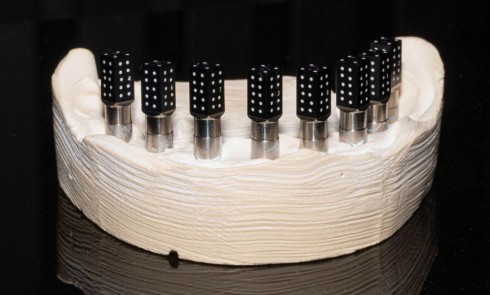

• Un volume anatomique 3D, ici « la dent », est réduit à une image 2D dite de projection par absorption sélective du rayonnement incident selon la nature des structures rencontrées.

– pour sa forme suivant l’orthogonalité ou l’obliquité du rayonnement par rapport au récepteur (fig. 1).

Une structure anatomique n’est radiologiquement visible que si le rayon directeur (axe du faisceau Rx incident) est tangent à cette structure. Une fracture radiculaire longitudinale ne sera mise en évidence qu’aux conditions d’une orientation favorable et de dimensions suffisantes (fig. 2).